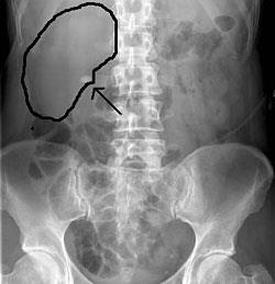

- Képalkotó tesztek. A képalkotó vizsgálatok veseköveket mutathatnak a húgyúti rendszerben. A lehetőségek az egyszerű hasüregi röntgentől, amelyből hiányozhatnak a kis vesekövek, a nagy sebességű számítógépes tomográfiáig (CT), amely még az apró köveket is feltárhatja. További képalkotó lehetőségek közé tartozik az ultrahang, a nem invazív teszt és az intravénás pyelográfia, amely magában foglalja a festék befecskendezését a kar vénájába, és röntgenfelvételeket készít, miközben a festék áthalad a vesén és a hólyagon.